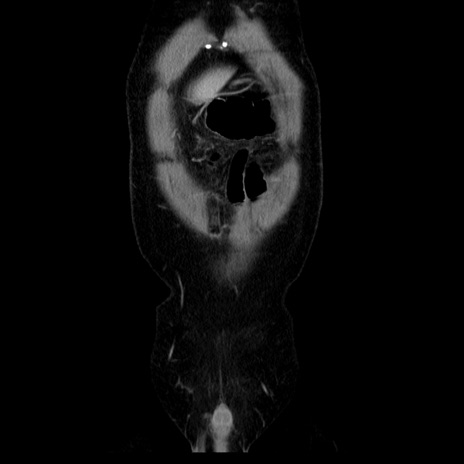

横断像